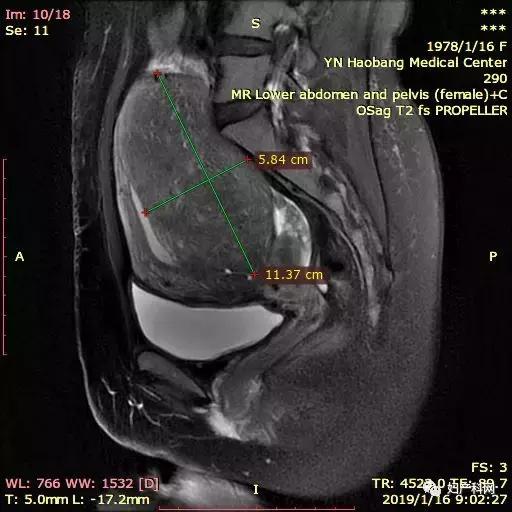

MRI如下:

因为这个患者子宫比较大,同时还有比较重的贫血貌,所以就诊时查了一下血常规仅有60+g/L,这样的情况下直接治疗不仅难度大,术后恢复也相对比较慢。所以我们先给予了患者一只10.8mg的诺雷德,希望她能够这几个月不来月经,避免进一步的丢失,同时开始口服铁剂补血,从1月底患者就诊到4月安排治疗,3个月的时间血色素恢复到了102g/L,子宫腺肌症的范围也从1月的12×7×11cm缩小到了8×5×7.5cm,治疗当天我们使用经皮的微波治疗,功率50w治疗6min10s,60w治疗9min36s,进行超声造影消融满意,于宫腔内放置了曼月乐环1枚。